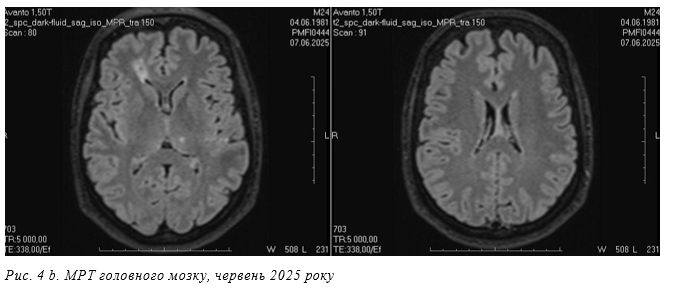

Кількість вогнищ попередня, появи нових вогнищ не визначається. Супутня знахідка: виявлене округле вогнище в зоні верхньої щелепи праворуч (верхній зубний ряд праворуч) при попередній МРТ наразі чітко не візуалізується. Визначається потовщення слизової оболонки верхньої щелепи праворуч до 6,8 мм. Контрольне МР обстеження через 2 роки показало позитивну динаміку, регрес вогнищевих змін головного мозку (рис. 4 а, b). 7.06.2025 МР виконані T2WI, DWI, SWI, T2_spc_ dark-fluid_iso, T1 MP-RAGE_iso, T1 MP- RAGE_iso + C сагітальні, корональні та аксіальні томограми головного мозку з подальшою мультипланарною реконструкцією. МР-картина множинного вогнищевого ураження супра- та інфратенторіальних відділів головного мозку, що за МР-характеристиками може більш ймовірно відповідати множинним внутрішньомозковим абсцесам в стадії регресу. Порівняно з попередньою МРТ від 26.01.2025 р. відсутнє накопичення контрасту окремих вогнищ, в решті

МР-картина залишається стабільною. Кількість вогнищ стабільна, появи нових вогнищ не визначається. Візуалізується пристінкове потовщення слизових оболонок обох верхньощелепних пазух до 3,0 мм, зліва кіста діаметром до 10 мм. Визначається округле вогнище в правій верхньощелепній пазусі (верхній зубний ряд праворуч) гетерогенного МР сигналу, загальним умовним діаметром 14,0 мм, з незначним неоднорідним переважно периферичним накопиченням контрастного препарату.